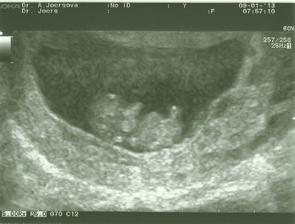

9.1.2013 poradna - bublinka má 2,66cm odpovídá 9+5tt